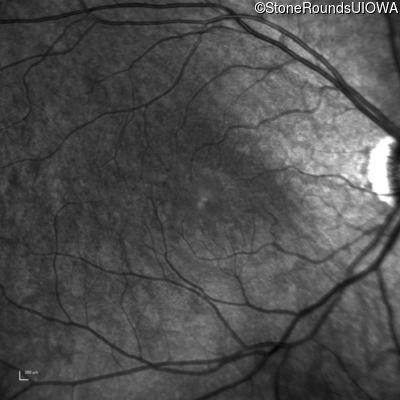

Infrared Fundus Photograph - Right - 20/40 +1

Exemplar